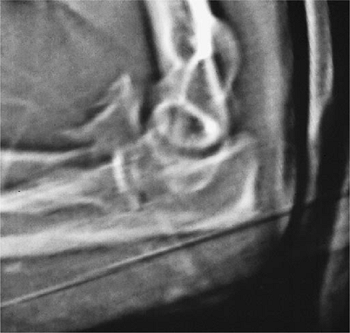

![]() |

Figure 7-16. This 40-year-old thoracic surgeon sustained a type II coronoid fracture after a fall from a bike.

a fracture dislocation of the left elbow. A type III coronoid fracture

was observed (Fig. 7-16). This was reduced and fixed with two 3.0-mm AO screws applied with the lag technique. A DJD II external fixator was applied (Fig. 7-17). At 8 weeks he has an arc of 40 to 130 degrees (Fig. 7-18). He returned to surgery at 10 weeks.